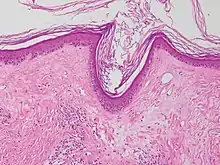

Micrograph of a vacuolar interface dermatitis with dermal mucin, as may be seen in lupus. H&E stain.

Vacuolar interface dermatitis (VAC, also known as liquefaction degeneration, vacuolar alteration or hydropic degeneration) is a dermatitis with vacuolization at the dermoepidermal junction, with lymphocytic inflammation at the epidermis and dermis.[1]